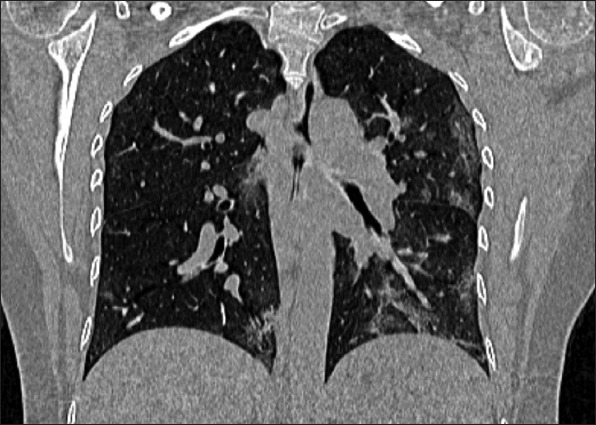

Results: A total of 31 case reports (level of clinical evidence: IV) of AAC related to COVID-19 were included. The mean age of patients was 64.7 ± 14.8 years, with a male-to-female ratio of 2.1:1. Major clinical presentations included fever 18 (58.0%), abdominal pain 16 (51.6%), and cough 6 (19.3%). Hypertension 17 (54.8%), diabetes mellitus 5 (16.1%), and cardiac disease 5 (16.1%) were among the common comorbid conditions. COVID-19 pneumonia was encountered before, after, or concurrently with AAC in 17 (54.8%), 10 (32.2%), and 4 (12.9%) patients, respectively. Coagulopathy was noted in 9 (29.0%) patients. Imaging studies for AAC included computed tomography scan and ultrasonography in 21 (67.7%) and 8 (25.8%) cases, respectively. Based on the Tokyo Guidelines 2018 criteria for severity, 22 (70.9%) had grade II and 9 (29.0%) patients had grade I cholecystitis. Treatment included surgical intervention in 17 (54.8%), conservative management alone in 8 (25.8%), and percutaneous transhepatic gallbladder drainage in 6 (19.3%) patients. Clinical recovery was achieved in 29 (93.5%) patients. Gallbladder perforation was encountered as a sequela in 4 (12.9%) patients. The mortality rate in patients with AAC following COVID-19 was 6.5%.